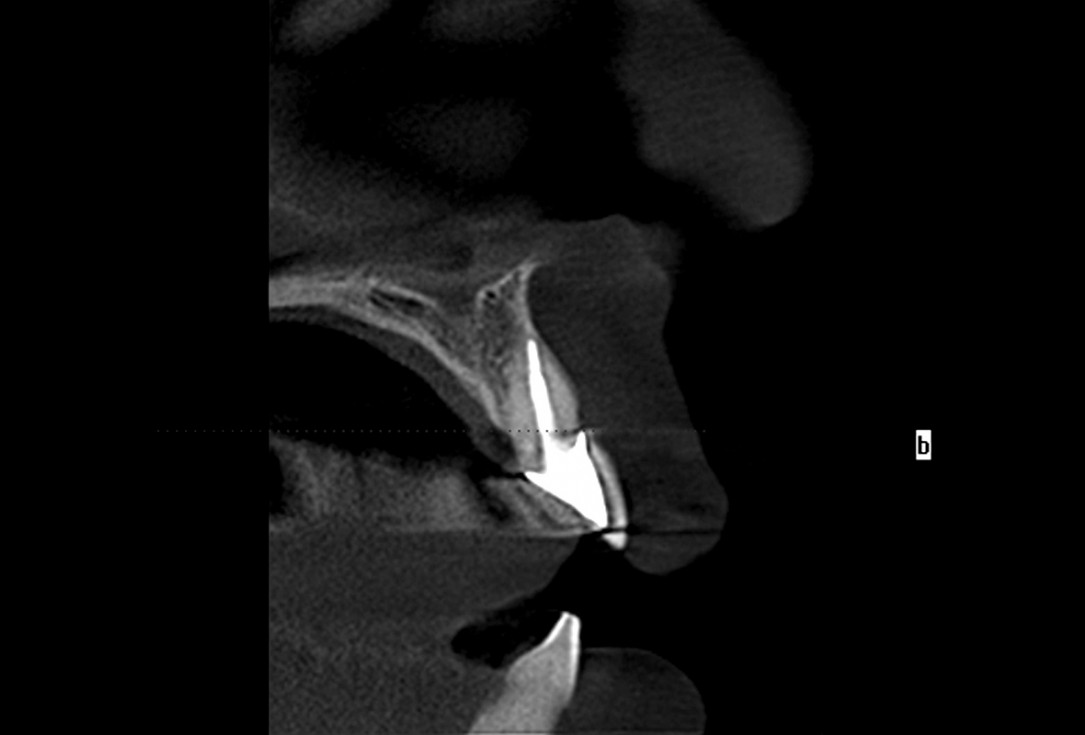

01/30 - Initial situationExcellent aesthetic result of buccal augmentation with mucoderm® and maxgraft® after immediate implant placement - 3-years follow-up - Dr. A. Puišys

02/30 - Initial situation, 36 year old ladyExcellent aesthetic result of buccal augmentation with mucoderm® and maxgraft® after immediate implant placement - 3-years follow-up - Dr. A. Puišys